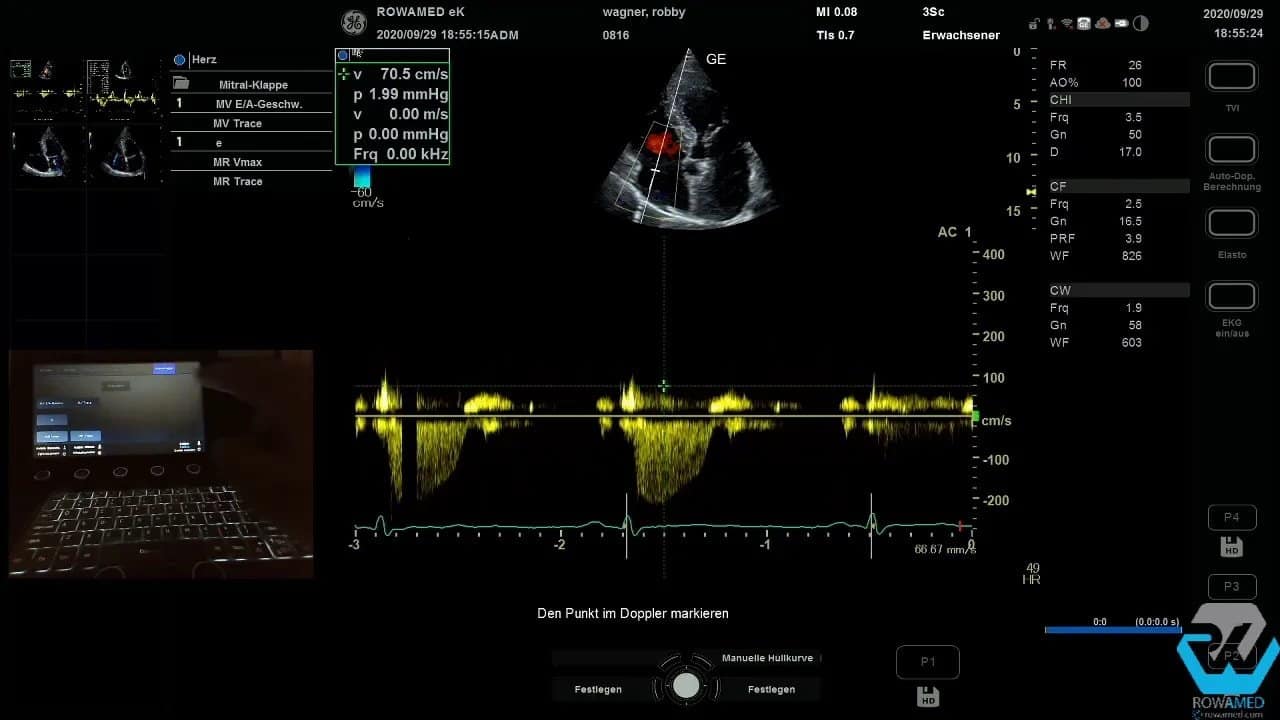

Step 10: Das Mitraleinstromprofil und die diastolische Funktion beurteilen

Die diastolische Funktion ist ein klassischer Bestandteil der Transthorakale Echokardiographie. Zunächst leiten Sie über den transmitralen Einstrom das E- und A-Wellen-Profil ab. Dafür wird im Messmenü auf die Mitralklappe umgestellt und dann die E-Welle, deren Dezelerationszeit sowie die A-Welle vermessen.

Technisch klappt das nicht immer beim ersten Versuch. Das ist kein Drama. Entscheidend ist, ruhig zu bleiben, das Messmenü korrekt zu wählen und die Kurve erneut sauber aufzunehmen. Im Beispiel ergab sich schließlich ein E/A-Verhältnis von 0,9, also ein unauffälliger Befund.

Für die weitere Einordnung einer möglichen diastolischen Dysfunktion wird anschließend der Gewebedoppler am medialen Mitralklappenanulus verwendet. Dort messen Sie das E‘. Aus E und E‘ lässt sich das Verhältnis E/E‘ berechnen. Dieses hilft bei der Abschätzung linksventrikulärer Füllungsdrücke.

Step 11: Klappeninsuffizienzen richtig einordnen

Bei der Mitralklappe zeigte sich ein relativ kräftig wirkender Jet, der an der Durchtrittsebene jedoch sehr schmal war. Das spricht für eine geringe bis allenfalls mittelgradige Mitralinsuffizienz. Genau an dieser Stelle passieren viele Fehleinschätzungen. Wer nur auf die Länge des Jets blickt, überschätzt leicht den Schweregrad.